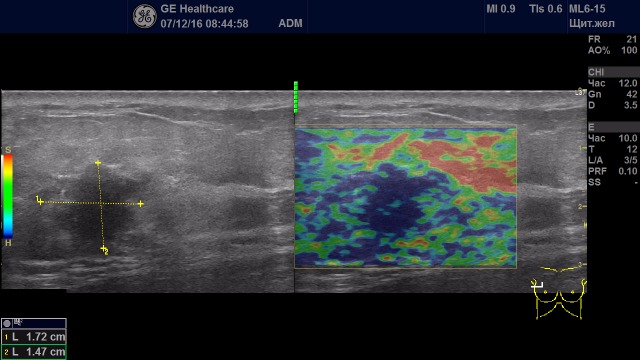

Образование с удовлетворительной эластичностью